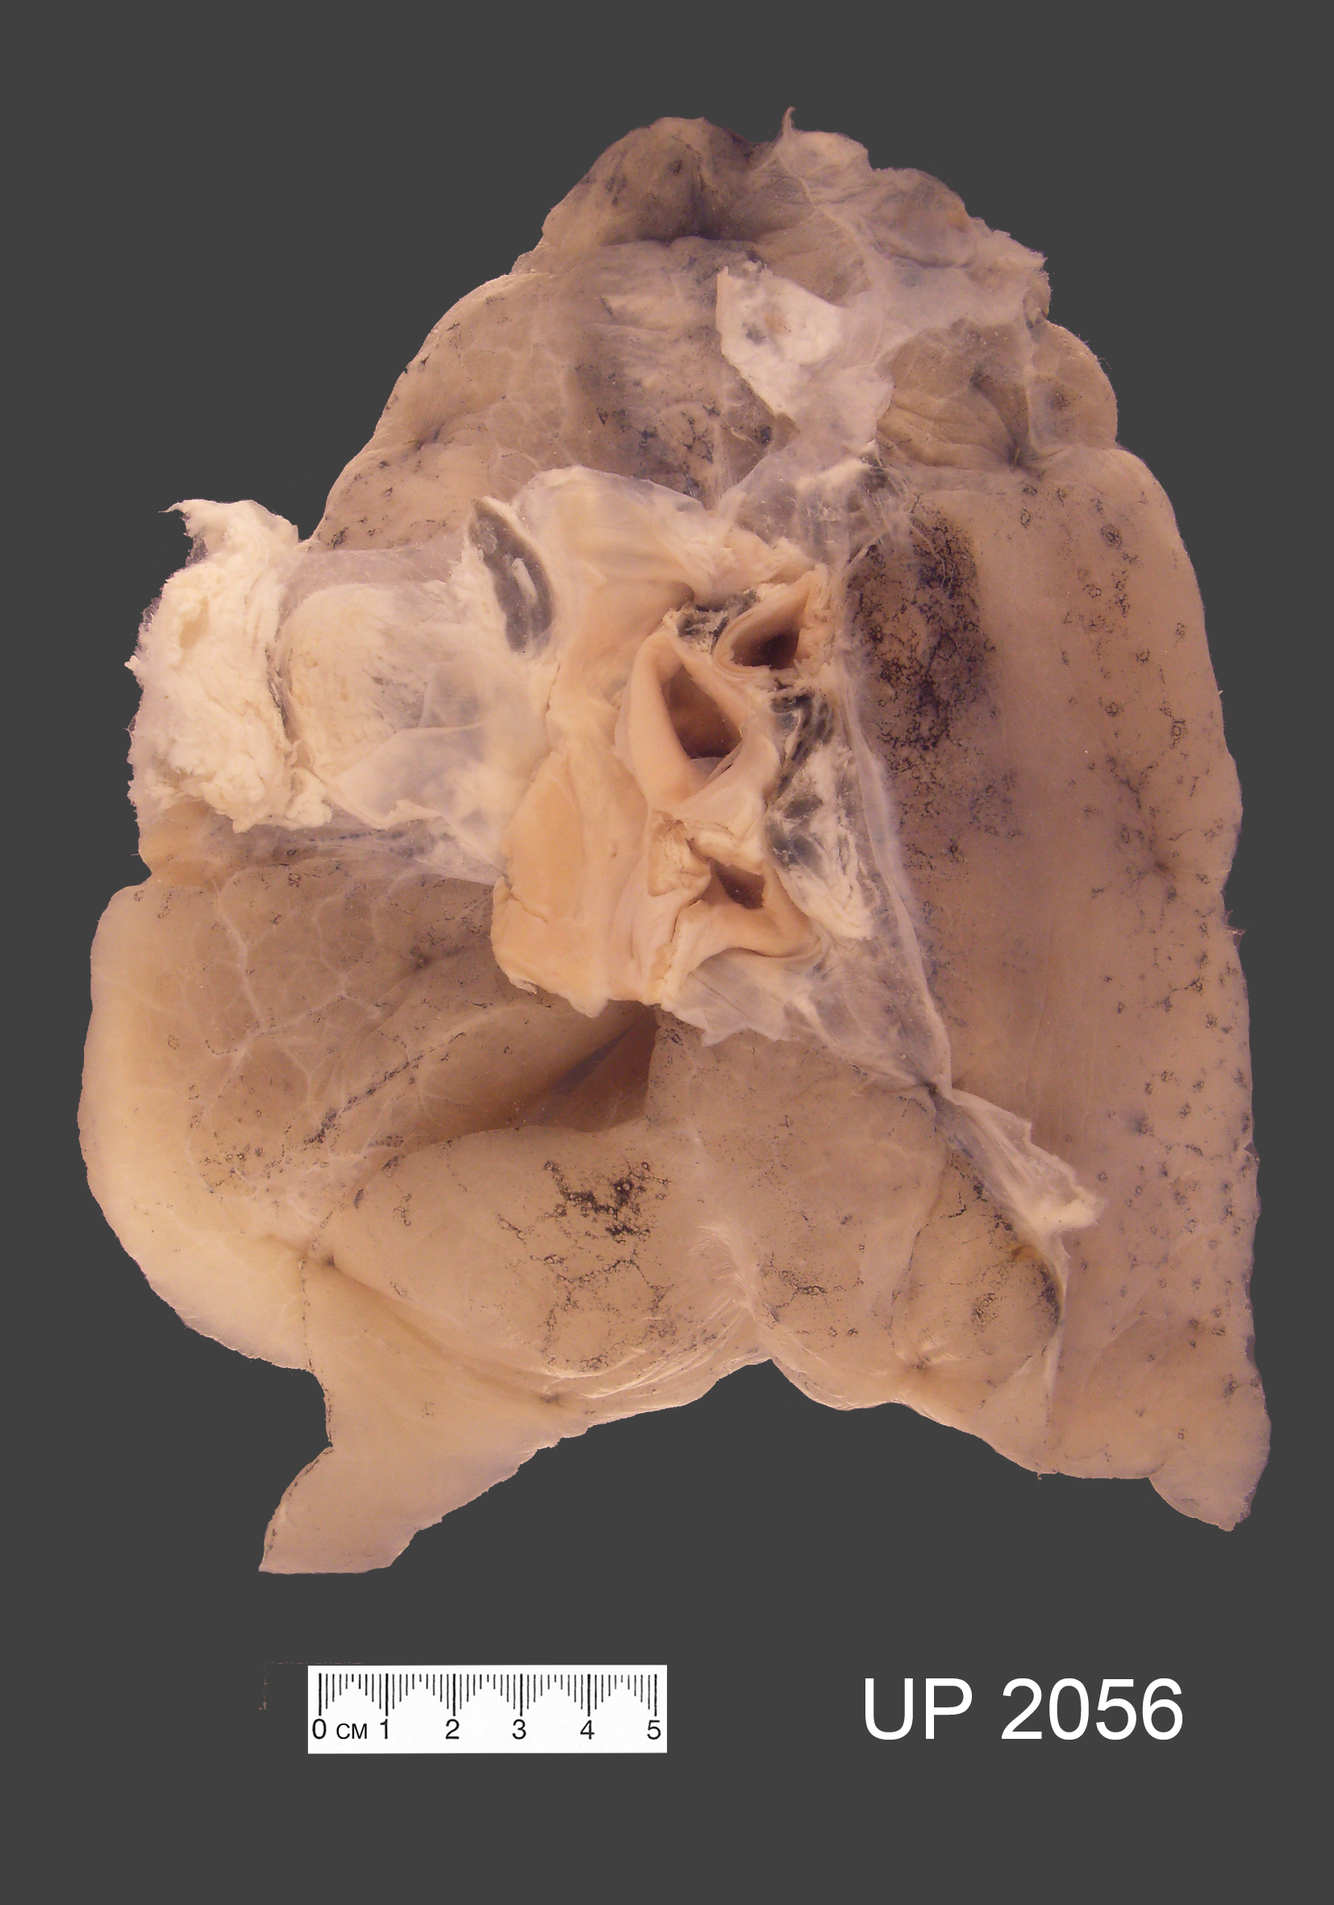

Describe the Specimen

The specimen shows a slice through the left lung, showing both upper and lower lobes.

The lung shows inflation classical of asthma

The bronchi appear prominent, with thickened walls and mucous plugging